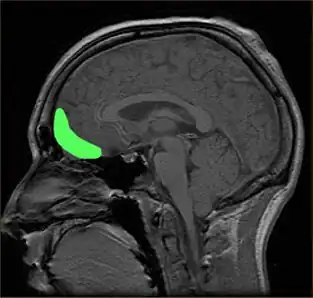

Prefrontal cortex

The prefrontal cortex is previously known for its roles in the perception of colored objects, decision making, and memory. Recent studies have also linked it to the conscious aesthetic experience because it is activated during aesthetic tasks such as determining the appeal of a visual stimuli. This may be because a judgment is needed, requiring visiospatial memory. In a study performed by Zeki and Kawabata, it was found that the medial orbito-frontal cortex (mOFC) is involved in the judgment of whether a painting is beautiful or not.[32] There is high activation in this region when a person views paintings which they consider beautiful. Other evidence shows that this same area is active during the experience of beauty derived from different sources,[42] including musical beauty[43] and moral beauty,[44] and even mathematical beauty.[45] Interestingly, experience of the sublime, as opposed to the beautiful, results in a different pattern of brain activity;[46] moreover, where it comes to judgment, although aesthetic and perceptual judgments leads t activity in the same brain areas, the pattern of activity is also different between the two, one of the most marked differences being the involvement of mOFC in aesthetic, but not in perceptual, judgments.[47] Surprisingly, when a person views a painting which they consider ugly, no separate structures are activated. Therefore, it is proposed that changes in the intensity of activation in the orbito-frontal cortex correlate with the determination of beauty (higher activation) or ugliness (lower activation). Additionally, the medial OFC has been found to respond aesthetics in terms of the context of which it is presented, such as text or other descriptions about the artwork. The current evidence linking the OFC to attributed hedonistic values across gustatory, olfactory, and visual modalities, suggests that the OFC is a common center for the assessment of a stimulus's value.[35] The perception of aesthetics for these areas must be due to the activation of the brain's reward system with a certain intensity.

Additionally, the prefrontal dorsalateral cortex (PDC) is selectively activated only by stimuli considered beautiful whereas prefrontal activity as a whole is activated during the judgment of both pleasing and unpleasing stimuli.[6] The prefrontal cortex may be generally activated for directing the attention of the cognitive and perceptual mechanisms towards aesthetic perception in viewers untrained in visual arts.[17] In other words, related directly to a person viewing art from an aesthetic perception due to the top-down control of their cognition. The lateral prefrontal cortex is shown to be linked to higher order self-referential procession and the evaluation of internally generated information. The left lateral PFC, Brodmann area 10, may be involved in maintaining attention on the execution of internally generated goals associated with approaching art from an aesthetic orientation.[17] As previously mentioned, directing of attention towards aesthetics may have evolutionary significance.